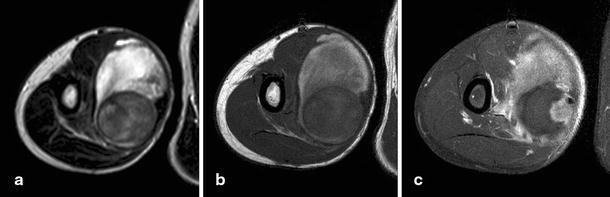

Pseuodaneurysms are an extremely rare complication of osteochondromas. We describe a case of traumatic pseudoaneurysm of the brachial artery presenting as a soft tissue mass in a patient who was treated for an osteochondroma 3 years earlier. This case demonstrates that radiographic follow-up of large osteochondromas is mandatory and that, in patients with soft tissue masses and a history of osteochondroma, pseudoaneurysms should be included in the differential diagnosis.

假性动脉瘤是软骨瘤的一种极罕见并发症。我们描述了一例创伤性肱动脉假性动脉瘤病例,该患者 3 年前因软骨瘤接受治疗,现表现为软组织肿块。该病例表明,对于大型软骨瘤必须进行放射影像学随访,如果患者有软组织肿块且有软骨瘤病史,则应将假性动脉瘤纳入鉴别诊断。